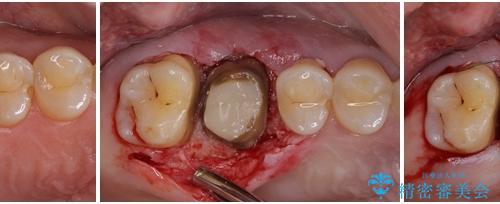

- クラウンが装着された奥歯から、歯磨きの度に出血するとのことで来院された患者様です。

虫歯が歯肉の奥深くにまで及んでおり、歯肉が腫れやすい状態となっていたため、歯肉の切除並びに歯槽骨の形態修正を行い、虫歯が歯肉の外に出てくるようにした上で、オールセラミックにて補綴することとしました。

歯間ブラシを通す度に出血をするのは、ご自身の磨き方が悪いからと思っていらっしゃいましたが、治療後は全く出血することがなくなり、患者様には大変満足していただきました。